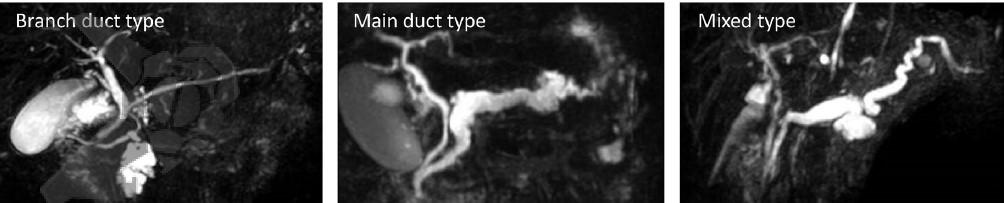

Não houve mudança em relação às definições dos três tipos de IPMN, que podem ser de ducto secundário (“Branch duct-IPMN” ou BD-IPMN), de ducto principal (“Main-duct IPMN” ou MD-IPMN) ou misto – quando contempla os critérios tanto para BD-IPMN quanto para MD-IPMN. Os cistos pancreáticos >5mm com comunicação com o DPP devem ser classificados como BD-IPMN, enquanto uma dilatação do DPP >5mm sem fator obstrutivo é classificado como MD-IPMN. A importância e manejo de cistos pancreáticos assintomáticos <5mm permanece controverso.